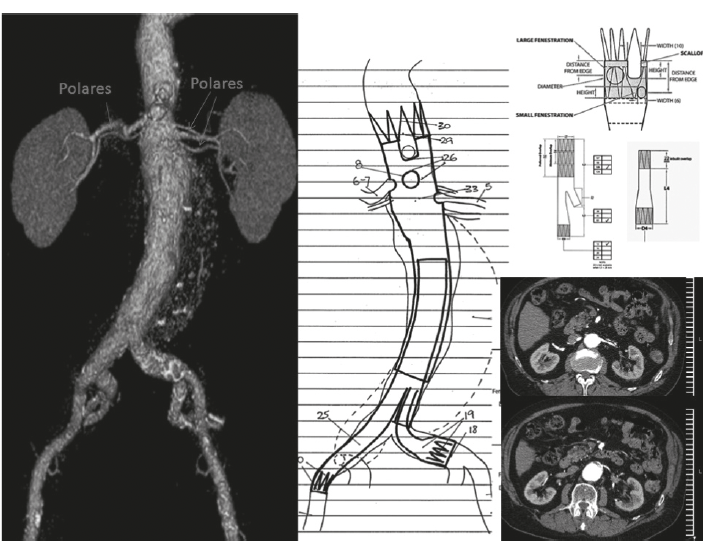

En los pacientes con un aneurisma de la aorta abdominal yuxtarrenal, el segmento normal de aorta infrarrenal necesario para lograr el anclaje proximal de una endoprótesis es insuficiente o inexistente, por lo que con las endoprótesis tradicionales no existe la posibilidad de sellar o excluir el aneurisma. Por este motivo, en los últimos años se han utilizado endoprótesis con fenestraciones (orificios) para la preservación de los ramos viscerales y renales como alternativa válida y menos invasiva.

En esta presentación se describe el primer caso de un aneurisma aórtico yuxtarrenal tratado en nuestro país mediante la colocación de una endoprótesis con múltiples fenestraciones. Se trata de un paciente de alto riesgo quirúrgico por comorbilidades clínicas, al cual con empleo de anestesia regional se le colocó una endoprótesis con fenestraciones para preservar la irrigación del tronco celíaco, la arteria mesentérica superior y ambas arterias renales. El procedimiento fue exitoso, lográndose la exclusión del aneurisma. El primer control posoperatorio demostró la exclusión del aneurisma con permeabilidad adecuada de los ramos viscerales.